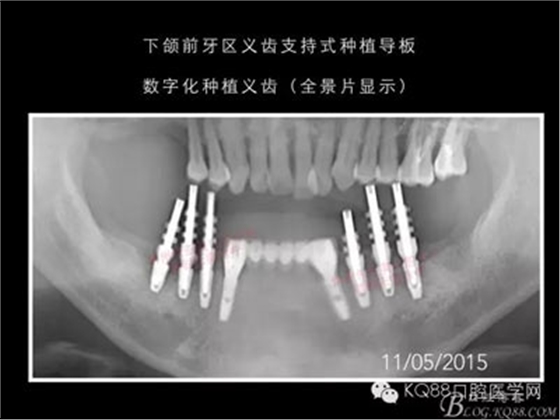

下面的種植病例是為患者提供全口牙齒治療修復(fù)完整過程的下頜部分,我們門診和患者共同配合下目前取得了較好的修復(fù)效果,即將開始的上頜牙齒治療修復(fù)過程仍然艱辛。